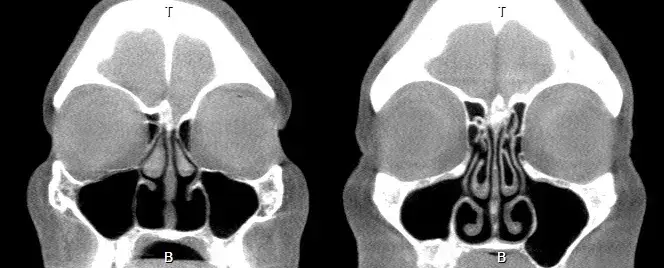

空鼻症的临床标志是“矛盾的鼻塞”,也就是从影像学和解剖上看,因缺乏下鼻甲而导致鼻的呼吸腔道宽大而明显,但是患者依然主诉“鼻子不通气”,或者有类似的难以言状的感觉,如感觉不到气流、气短、呼吸困难,甚至要求辅助通气设备来解决“气促”问题。

正常的鼻腔,有上、中、下三个鼻甲,其中下鼻甲参与构成了鼻腔中最狭窄和柔软的通道组成。